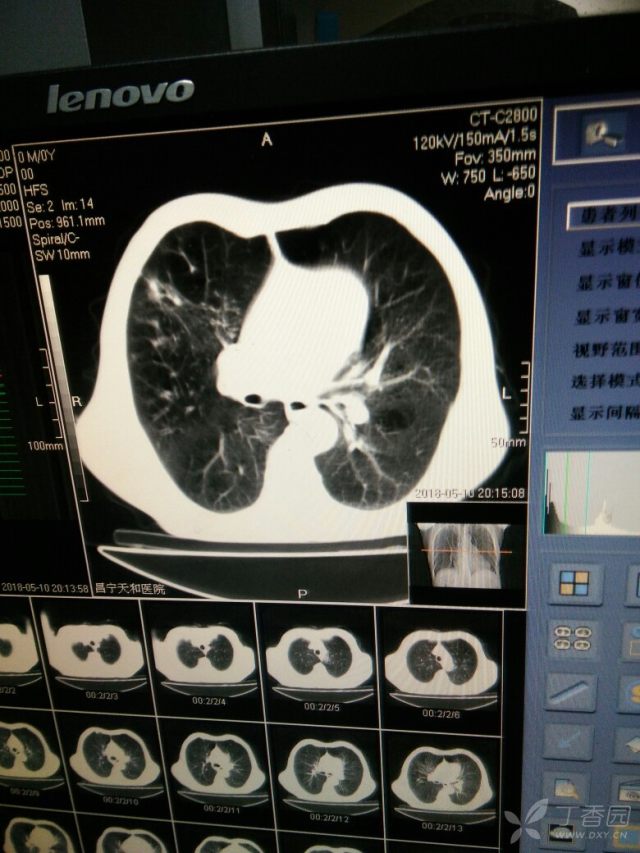

肺部有阴影是什么原因,肺部有阴影CT

肺部阴影

肺部有阴影CT

肺部有阴影

肺部阴影诊断

肺部阴影有几种可能

肺部阴影片子

肺部阴影图片

肺部ct